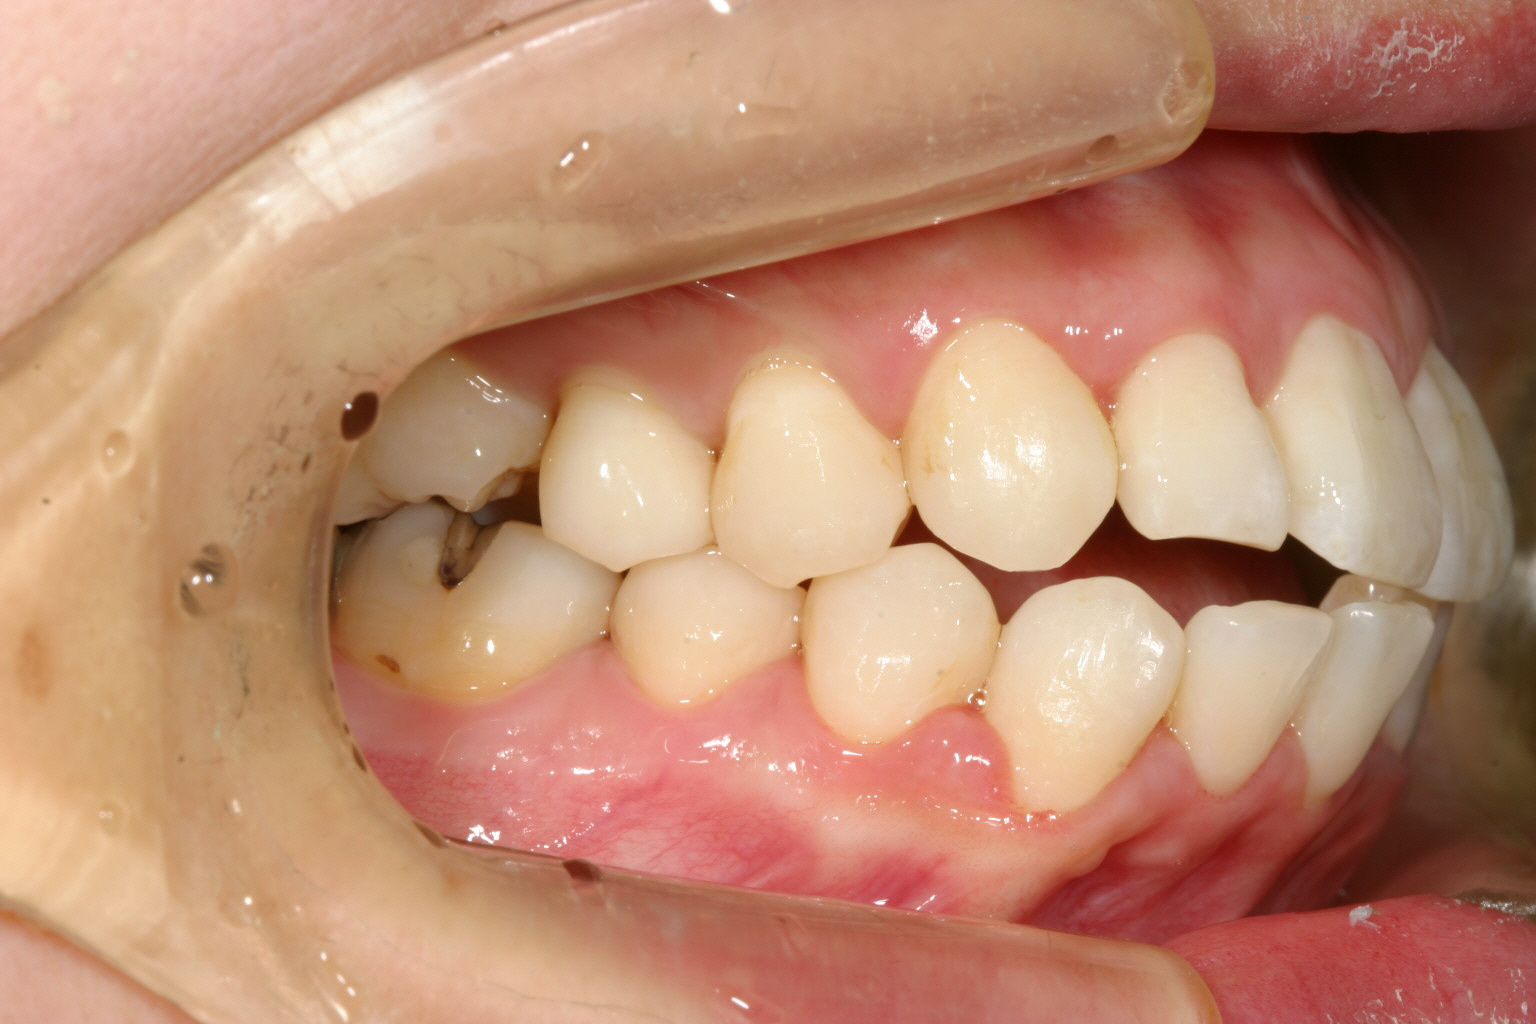

右側の犬歯の飛び出しが少し気になりますね~

下顎前歯は犬歯間幅径が狭い為ヘビーなガタガタです。

上下顎のオーバージェットが気になります。